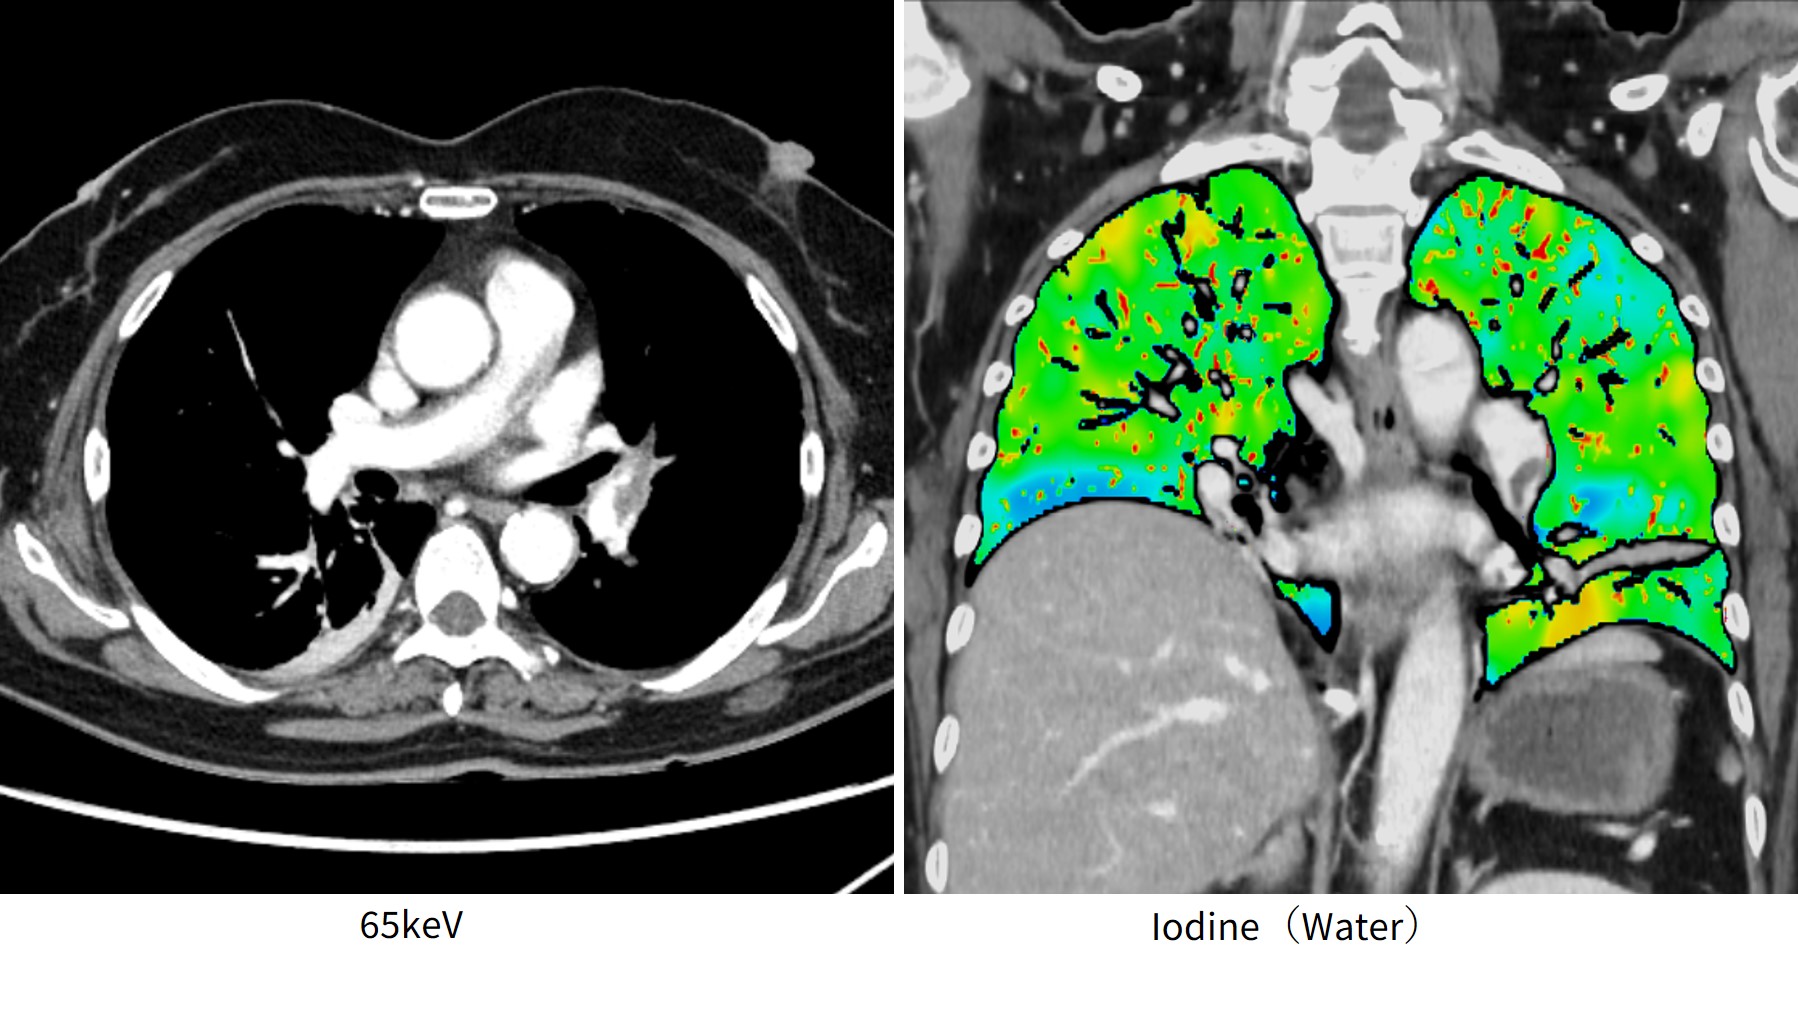

症例2)肺塞栓

熱源検索で全身撮影を実施し、偶発的に肺塞栓が認められた所見である(Fig.4)。肺塞栓目的に検査を行っていないため、造影に関しては520mgI/kg・50秒間注入し、注入終了してから30秒後に撮影を行っている。高速注入でなくても、仮想単色X線画像により造影効果を上げることができ、肺塞栓を判別できる。偶発的に見つかった所見でも、DE撮影がルーチンのため、肺灌流画像の作成が可能であった。

revolutionapexelite_aomori08.jpg

Fig.4 偶発的に見つかった肺塞栓